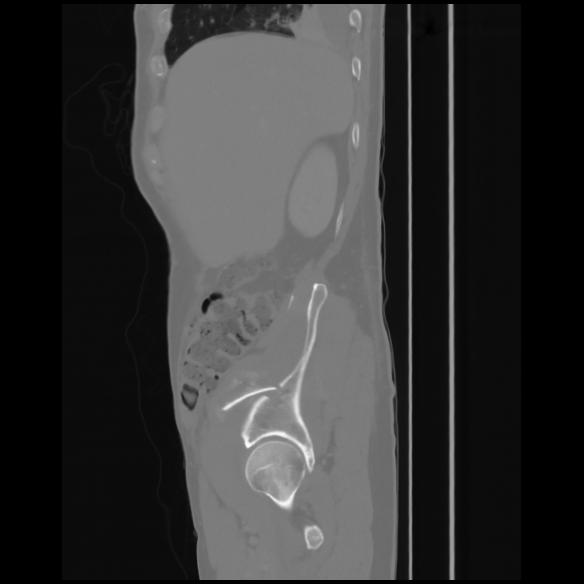

7 CUERPO,CE,Sagittal,3.000,CUERPO,Sagittal,